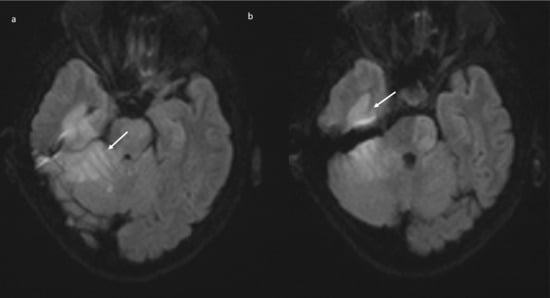

Brain magnetic resonance imaging (MRI) in the same day showed the presence of an acute basilar thrombosis (Figure 5a) associated with the superior sagittal sinus thrombosis (Figure 5b) with the delineation of hyperacute ischemic lesions in the vascular territory of the right posterior cerebral artery and of the perforating pontine branches (Figure 6).

Figure 5.

MR-angiography: acute basilar thrombosis associated with superior coronal (a) and sagittal (b) sinus thrombosis.

Figure 6.

Brain MRI (DWI): acute ischemic lesion with restricted diffusion involving the pons, mesencephalon, the right superior cerebellar hemisphere with the vermis (a), and the right posterior temporal lobe (b).